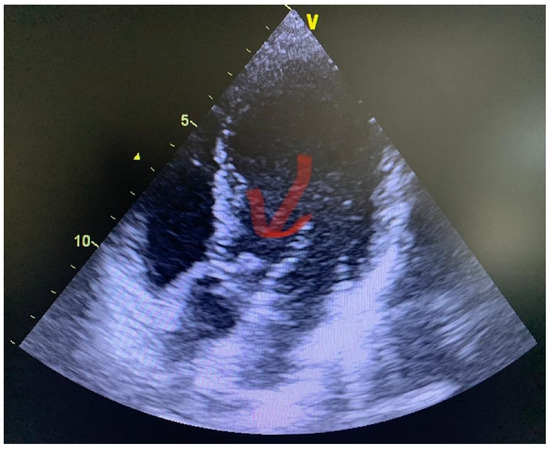

2. Case Presentation